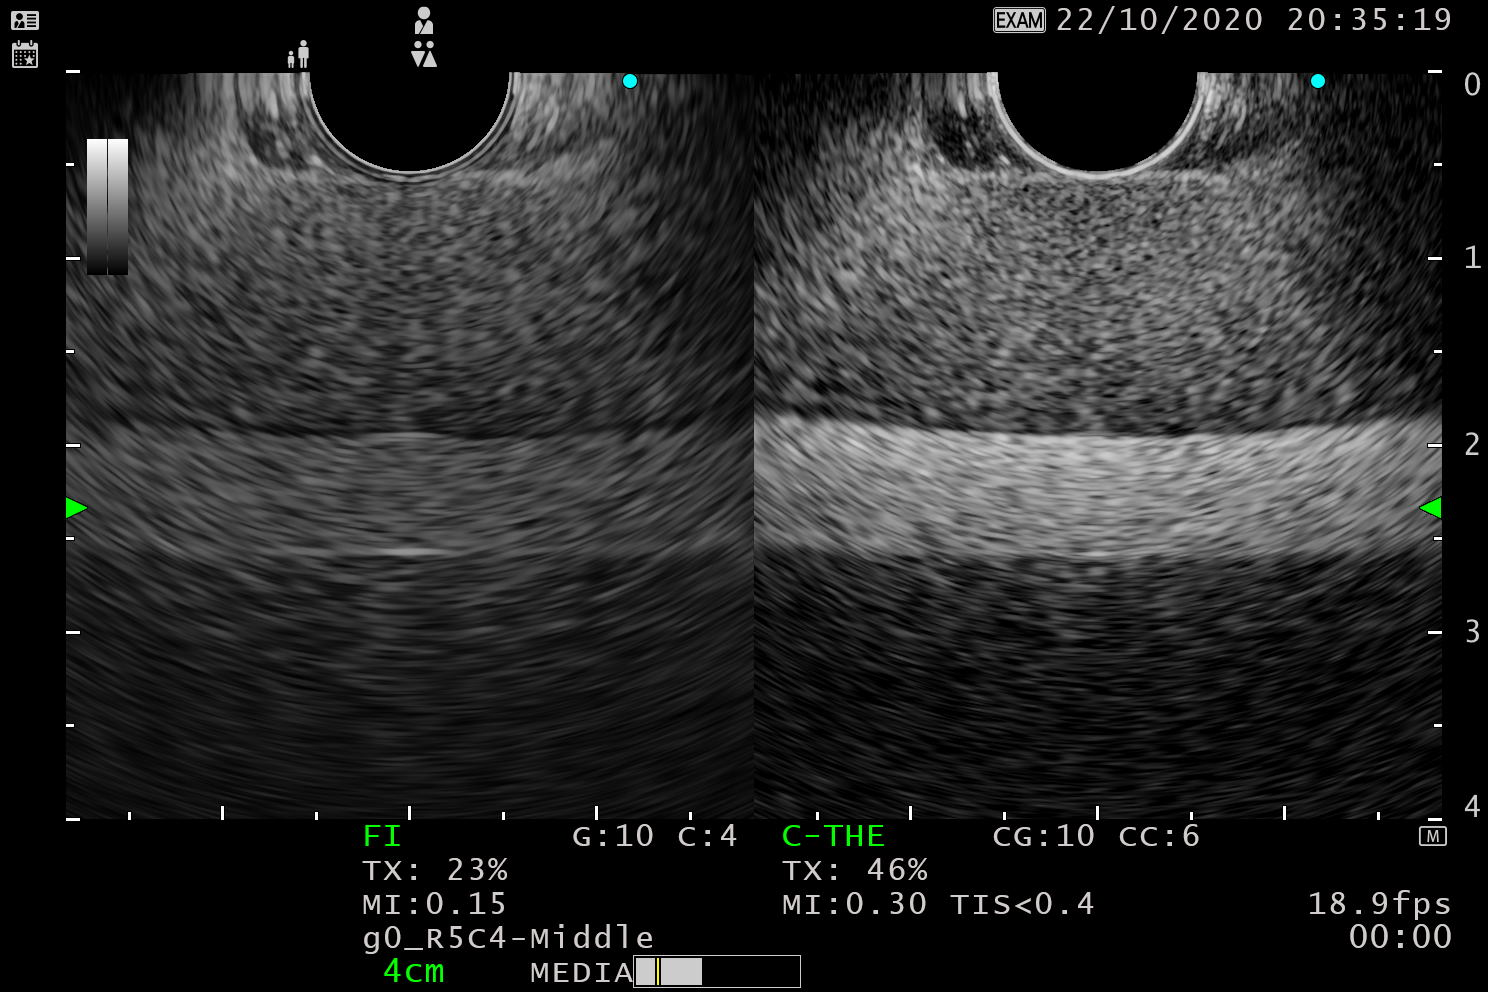

使用 B 模式或更高階的THE模式生成超音波影像

B 模式

與EU-ME2相比,解析度和穿透深度均有所提升。

以下為兩款機型分別連接 BF-UC290F 的畫面。

THE 模式

利用高諧波提升影像解析度,減少偽影(Artifacts),以精準診斷膽囊、膽管。